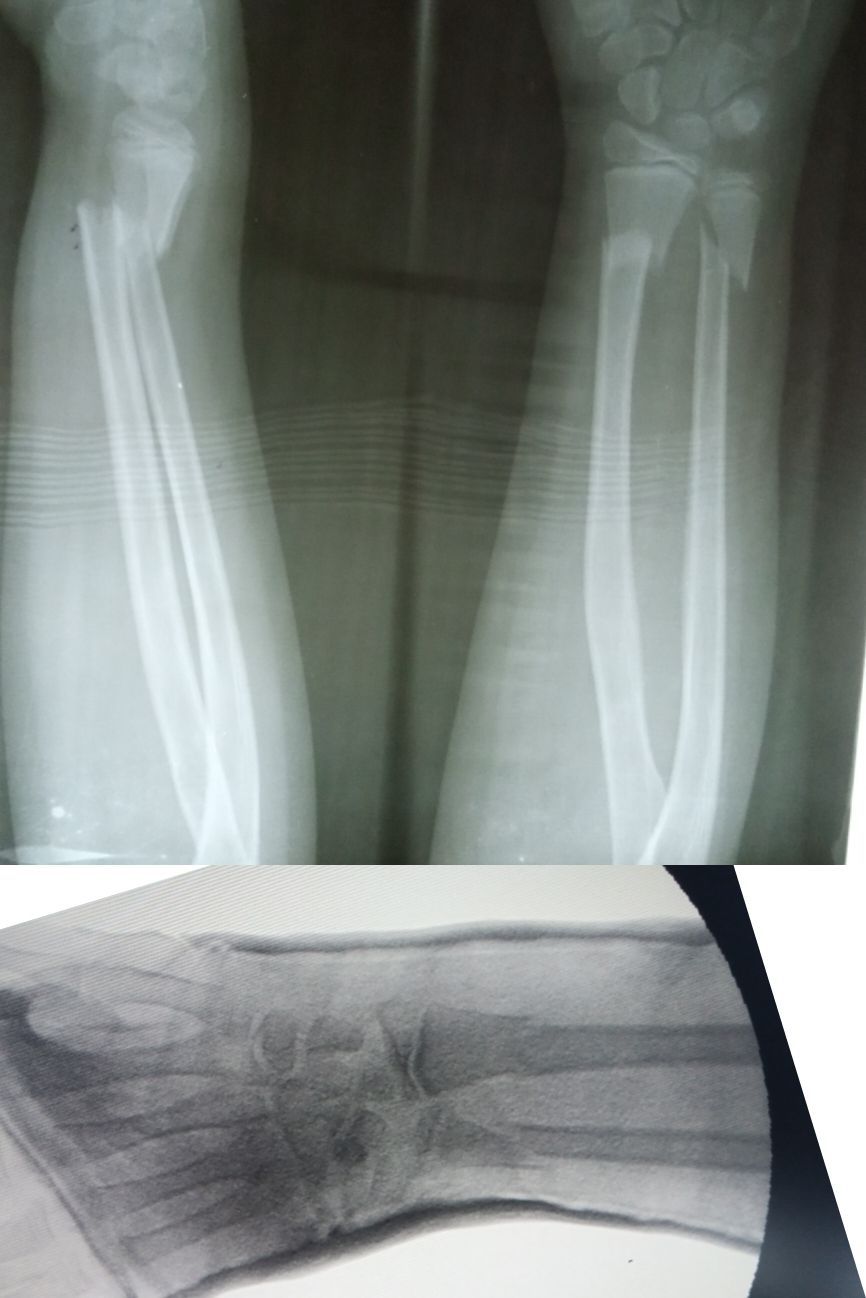

Fx distal radius & ulna

MUA done e POP cast